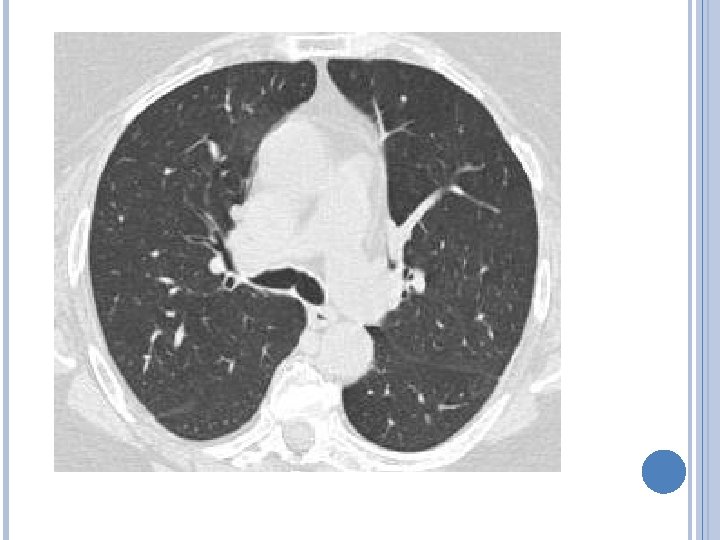

IMAGENES